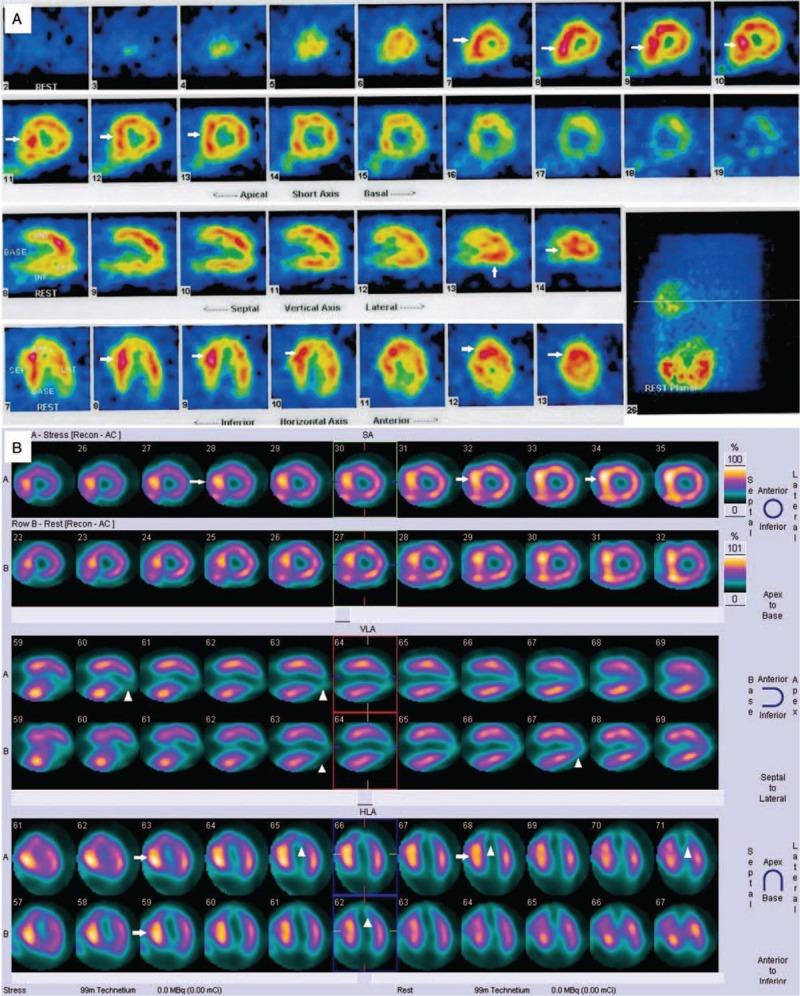

A 33-year-old man who presented with chest discomfort for 10 days. He had an emerging apical aneurysm in the LV without midventricular obstruction. He had been diagnosed with apical HCM via abnormal electrocardiograms (ECG) and single-photon emission computed tomography (SPECT) for 10 years. This time, a new significant change in ECG and SPECT was identified. Late gadolinium enhancement (LGE) was observed by cardiac magnetic resonance imaging (MRI), and SPECT showed myocardial fibrosis or necrosis involving the apical aneurysm and proximal portion of the heart, which was confirmed by left ventriculography.

一名33岁男性,因胸部不适10天前来就诊。他左心室出现了一个新的心尖部动脉瘤,无室中隔梗阻。他通过异常心电图(ECG)和单光子发射计算机断层扫描(SPECT)被诊断为心尖部HCM已有10年。此次,ECG和SPECT出现了新的显著变化。心脏磁共振成像(MRI)观察到晚期钆增强(LGE),SPECT显示心肌纤维化或坏死累及心尖部动脉瘤及心脏近端部分,左心室造影证实了这一点。